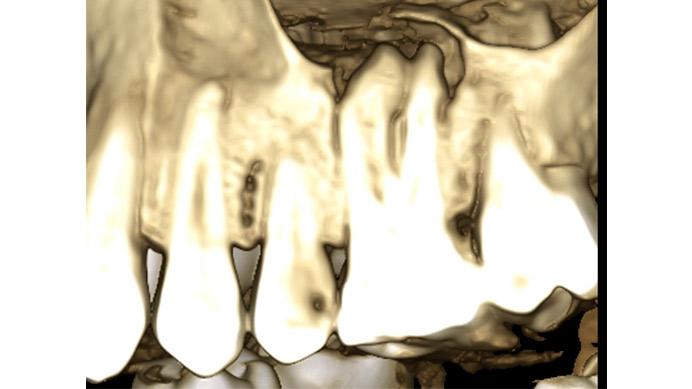

Ian es un paciente que nos cuenta su experiencia tras una intervención de cirugía periapical. Ian vino a la clínica dental IDIM con molestias en una muela superior que en el estudio radiográfico se vio que presentaba infección a causa del fracaso de una endodoncia.

Se decidió realizar una cirugía periapical para eliminar la infección y sellar las raíces con un empaste para evitar que volviera a tener problemas. Gracias a esta efectiva intervención Ian conserva su muela, lo cual es preferible, siempre que se puede, a tener que extraerla y sustituirla con un implante dental.